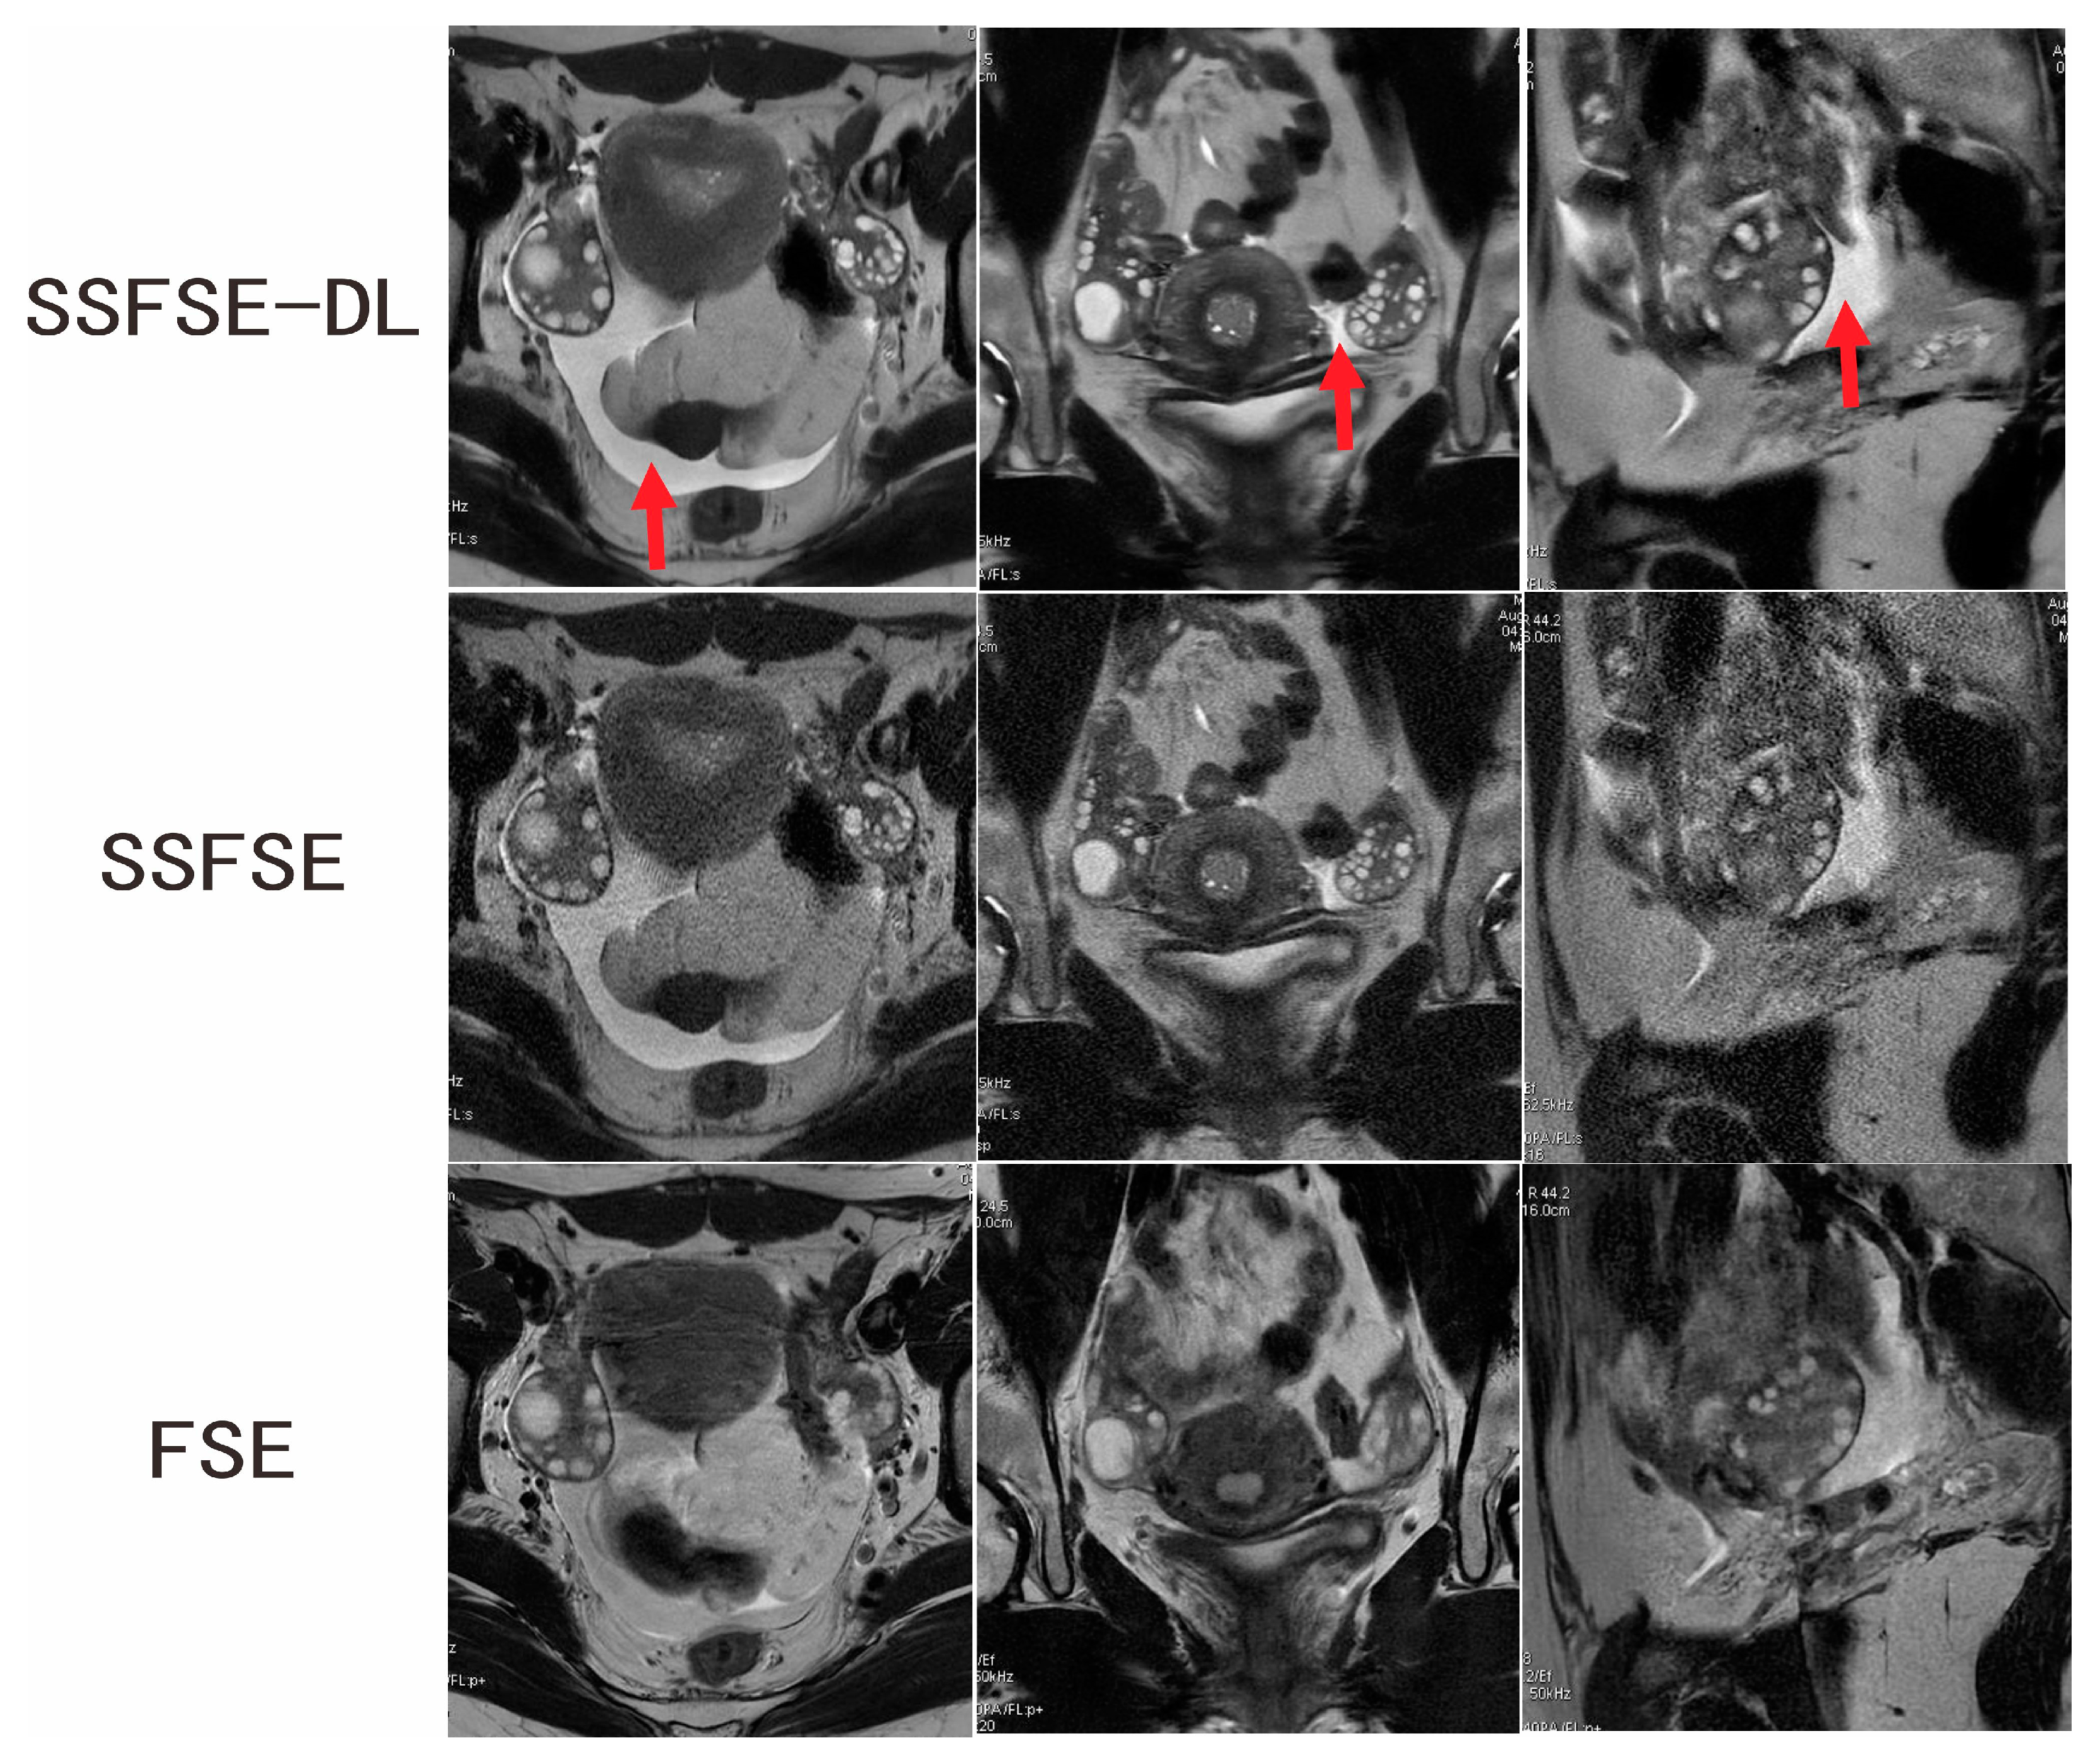

Figure 1.

Ovarian MRI in a 16-year-old adolescent girl with confirmed PCOS. SSFSE-DL images (upper row) show the lowest noise, blurring artifacts, and the bilateral enlarged ovaries with a dominant follicle and many small follicles. The pelvic fluid collection (arrow) is easily detected on the SSFSE-DL images. Noise is prominent on the SSFSE images (middle row). The FSE images (lower row) mainly showed blurring artifacts caused by respiratory and bowel motility.